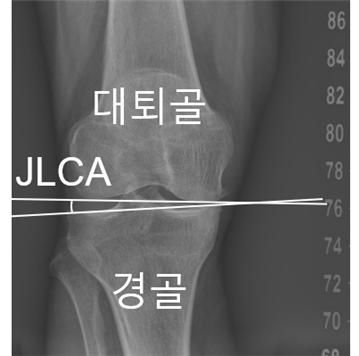

¡ã ¹«¸ °üÀý¼± ¼ö·Å°¢(JLCA)

¹«¸ °üÀýÀÇ Á¤·Ä »óŰ¡ º¯ÈÇÏ´Â ¾ç»ó°ú ±× º¯Çü ¼Óµµ¿¡ ¿µÇâÀ» ¹ÌÄ¡´Â ÇÙ½É ¿äÀÎÀÌ È®ÀεƴÙ. ¼¿ï´ëº´¿ø ¿¬±¸ÆÀÀº ¹«¸ °üÀýÀ» ÀÌ·ç´Â »À°¡ ¹ú¾îÁø Á¤µµÀÎ ¡®°üÀý¼± ¼ö·Å°¢(JLCA)¡¯ÀÌ ÀÌ·¯ÇÑ º¯ÇüÀ» °¡¼ÓÈÇÏ´Â °áÁ¤Àû ÁöÇ¥¶ó°í ¹àÇû´Ù.

¿¬±¸ÆÀÀº ÀΰøÁö´É ±â¹Ý ¼ÒÇÁÆ®¿þ¾î¸¦ Ȱ¿ëÇØ ȯÀÚÀÇ ÇÏÁö ¿¢½º·¹ÀÌ »çÁøÀ» ºÐ¼®Çß´Ù. À̸¦ ÅëÇØ ¾ûµ¢ÀÌ-¹«¸-¹ß¸ñ °¢µµ(HKAA), °üÀý¼± ¼ö·Å°¢(JLCA), °üÀý¿° ÁßÁõµµ(K-L µî±Þ) µî ÁÖ¿ä ÁöÇ¥¸¦ ÃøÁ¤Çß´Ù. ´Ù¸®°¡ ÈÖ¾îÁø Á¤µµÀÎ HKAA¸¦ ±âÁØÀ¸·Î ÇÏÁö¸¦ ¡ãOÀÚÇü ¡ãÁ߸³ ¡ãXÀÚÇüÀ¸·Î ±¸ºÐÇϰí, Á¤·Ä º¯È°¡ ¿¬°£ 0.5¡Æ ÀÌ»óÀÎ °æ¿ì¸¦ ¡®°¡¼Ó ÁøÇ࡯À¸·Î Á¤ÀÇÇØ Á¤·Ä º¯È ¾ç»ó°ú ¿µÇâ ¿äÀÎÀ» ºÐ¼®Çß´Ù.

¿¬±¸ÆÀÀº ¹«¸ °üÀýÀ» ÀÌ·ç´Â ´ëÅð°ñ°ú °æ°ñ »çÀÌÀÇ °üÀý¼±ÀÌ ¹ú¾îÁø Á¤µµÀÎ ¡®°üÀý¼± ¼ö·Å°¢(JLCA)¡¯ÀÌ ÀÌ·¯ÇÑ °¡¼Ó ÁøÇàÀ» ¿¹ÃøÇÏ´Â °øÅë ÁöÇ¥ÀÓÀ» ¹àÇô³Â´Ù. Ãʱ⿡ ÃøÁ¤µÈ JLCA°¡ 1¡Æ Ä¿Áú ¶§¸¶´Ù OÀÚÇü ȯÀÚ¿¡¼ 12.9%, XÀÚÇü ȯÀÚ¿¡¼ 19.4%¾¿ °¡¼Ó ÁøÇà À§ÇèÀÌ Áõ°¡Çß´Ù. ƯÈ÷ OÀÚÇü ȯÀÚÀÇ °æ¿ì °üÀý¿° ÁßÁõµµ°¡ ³ôÀ»¼ö·Ï °¡¼Ó ÁøÇà À§ÇèÀÌ Áõ°¡ÇßÀ¸¸ç, Áߵ ÀÌ»ó(Grade III, IV) ´Ü°è¿¡¼´Â Á¤»ó±º(Grade 0) ´ëºñ ¾à 4~5¹è ³ôÀº °ÍÀ¸·Î ³ªÅ¸³µ´Ù.